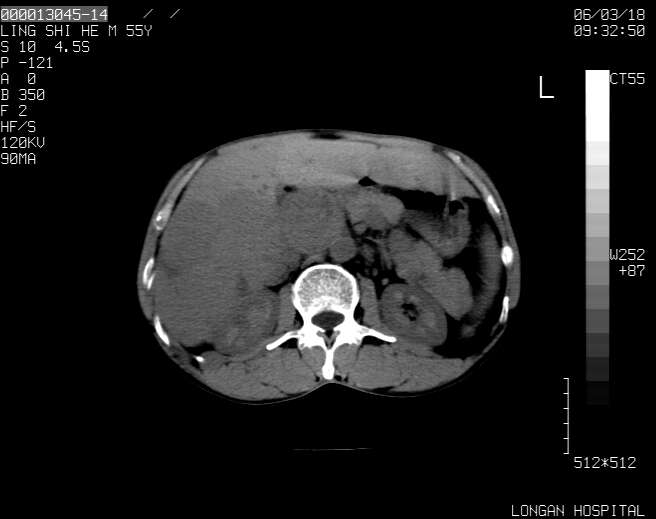

以下是引用guzhongliangddd在2006-3-21 22:13:00的发言:[br]病灶主要位于肝右叶的后份,内见异常血管,门脉主干及右支受侵{提示有癌栓形成},门腔间隙内见增大淋巴结。肝左叶内未见异常。

以下是引用zhuxinli在2006-3-22 1:23:00的发言:[br][br] 病灶主要位于肝右叶的后份,内见异常血管 .门脉右支截断,右叶前段早期强化(考虑动静脉漏),腹膜后肿大淋巴结,病灶逐渐强化,考虑为胆管细胞癌[br]